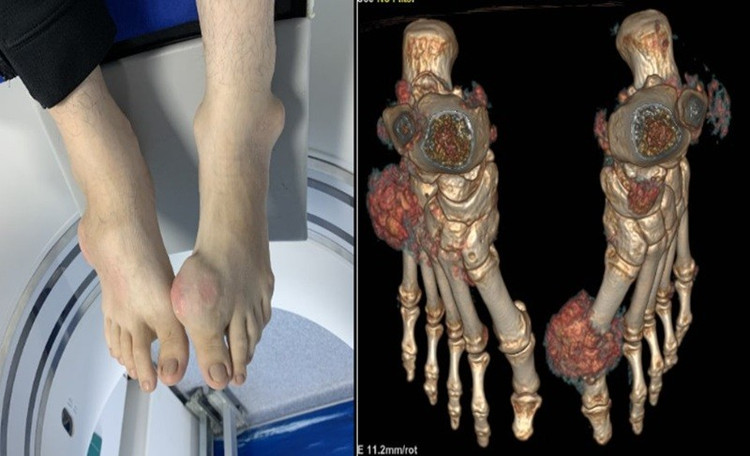

Tại thời điểm thăm khám, bác sĩ ghi nhận bệnh nhân tỉnh, tiếp xúc tốt, chỉ số BMI 27,6 (béo phì độ I). Hai bàn chân bệnh nhân có biến dạng khớp nặng, đặc biệt tại khớp bàn ngón chân cái hai bên. Nhiều khối tophi kích thước lớn lồi gồ dưới da, ranh giới không rõ, làm thay đổi trục khớp. Da vùng khớp căng, dày, một số vị trí đỏ nhẹ.

Khớp bàn ngón chân, ngón tay của bệnh nhân bị biến dạng nặng do biến chứng của bệnh gút mạn tính/ Ảnh Medlatec

Siêu âm khớp cổ chân phải ghi nhận hình ảnh theo dõi hạt tophi kèm tình trạng viêm phần mềm và tràn dịch khớp. Đặc biệt, kết quả chụp cắt lớp vi tính hai mức năng lượng (DECT) bàn chân cho thấy, nhiều ổ tiêu xương tại cổ chân, xương bàn - ngón và xương chêm hai bên. Hình ảnh lắng đọng tinh thể urat lan tỏa tại bao hoạt dịch, gân cơ và phần mềm vùng cổ chân, bàn chân, ưu thế ở bàn chân phải và khớp bàn – ngón I chân trái.

Hình ảnh lắng đọng tinh thể urat lan tỏa tại bao hoạt dịch, gân cơ và phần mềm vùng cổ chân, bàn chân… qua chụp DECT/Ảnh Medlatec